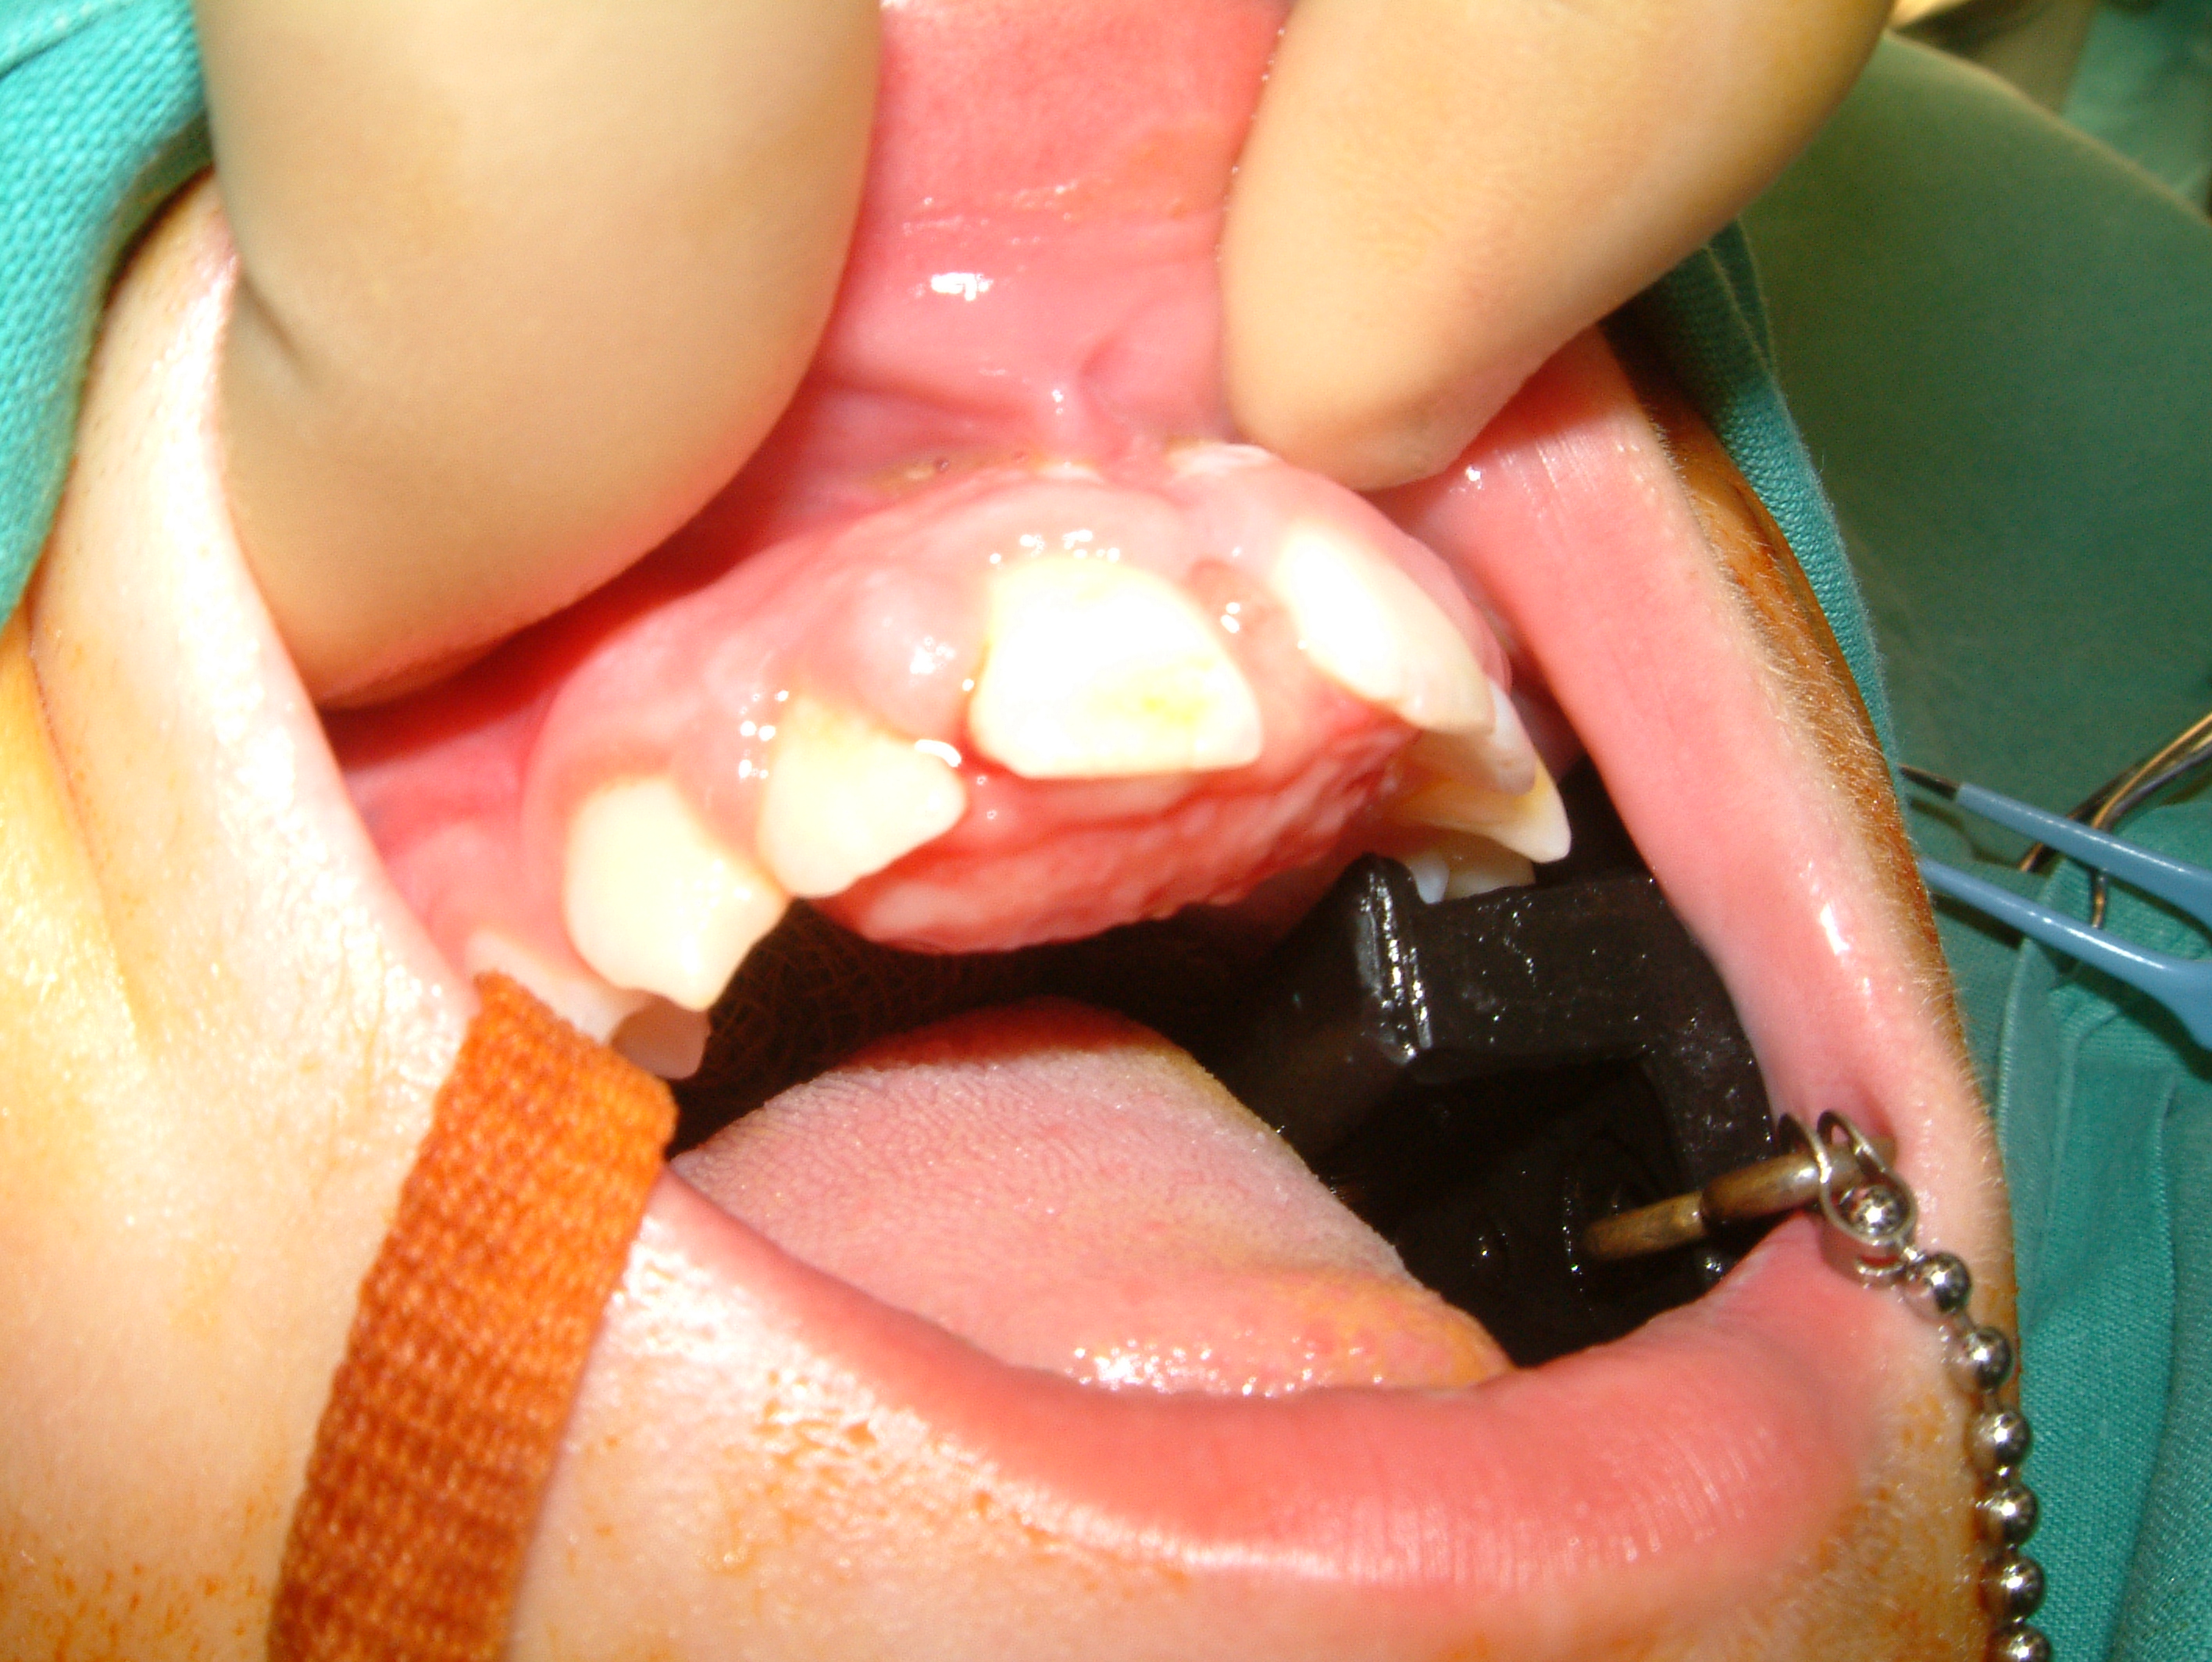

Another example of a common, benign vascular tumour that is closely related to haemangioma is pyogenic granuloma (Figure 2). Pyogenic granuloma often affects the gingiva (the gums), may cause discomfort or pain and bleeding and thus may require intervention(s).

Figure 2: Pyogenic granuloma of the palate.